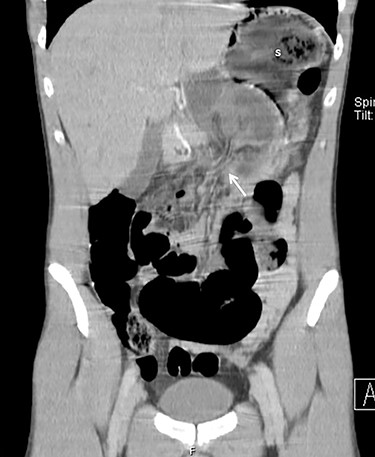

The abdomen had a tympanic percussion in the upper quadrants and tenderness in the epigastric area. He also presented with tachycardia, without other relevant findings. The laboratory studies revealed increased white blood cell count (WBC) and air-fluid levels on the abdominal x-ray (Fig. 1). Due to high suspicion of small bowel obstruction, an abdominal computed tomography was performed, revealing signs of an internal hernia of unknown type (Fig. 2).

Axial CT images of dilated small bowel (sb) with the respective mesentery converging to the hernia defect (white arrow) in the gastrohepatic ligament.